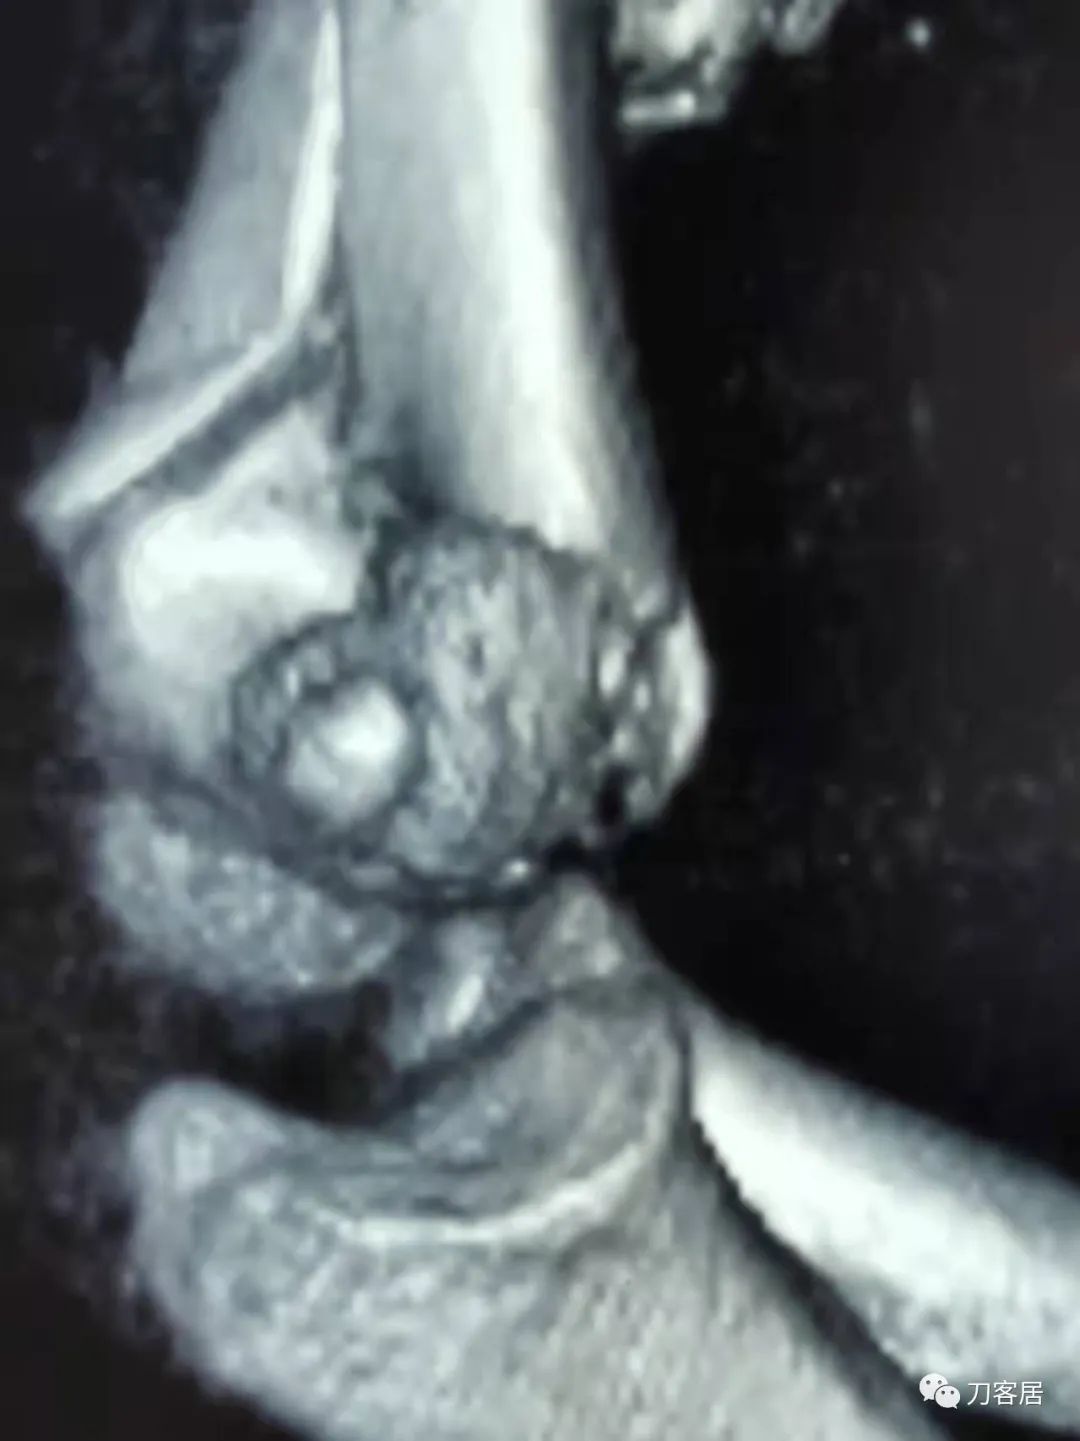

20210922当地省中医院三维CT01

20210922当地省中医院三维CT02

20210922当地省中医院三维CT03

20210922当地省中医院三维CT04

查体:左侧肘关节肿胀明显、疼痛、畸形,局部可见明显青紫瘀斑,左肘关节活动受限,肱骨远端环形压痛(+),局部可及异常活动及骨擦感形成,左上肢末梢桡动脉可触及,左侧腕关节及拇指背伸活动受限,左侧虎口区感觉麻木。辅助检查:自带X线及CT片示:左肱骨髁间粉碎性骨折。

入院诊断:1. 左肱骨髁间粉碎性骨折;2.左肱骨远端骨骺损伤;3. 左桡神经损伤。